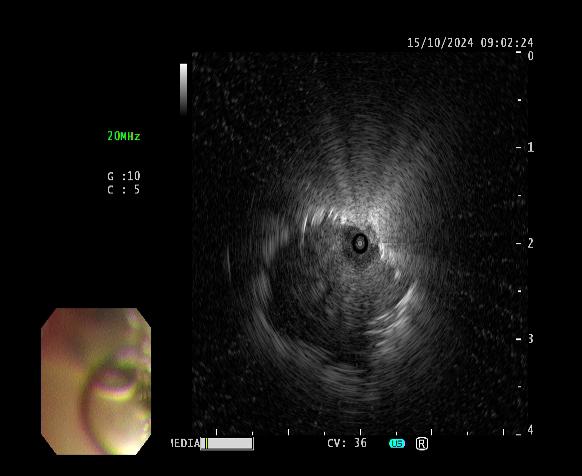

患者女性,因“气短1月”来门诊就诊,为明确诊断进一步治疗,收入MILAN.COM。入院后完善相关检查,胸部CT示左肺上叶前段高密度灶,与家属充分沟通后,决定为患者行超声支气管镜检查。主任医师吴水淼与主管护师薛冬冬为患者行气管镜检查,镜下示:双肺支气管均未见明显异常,结合CT给予超声探查,于左肺上叶前段亚支探及偏心异常回声区,由于亚支位置较高且管腔较窄,活检钳无法到达,给予冷冻肺活检。此次检查过程顺利,成功获取2块活检标本,活检病理结果提示为粘液腺癌。